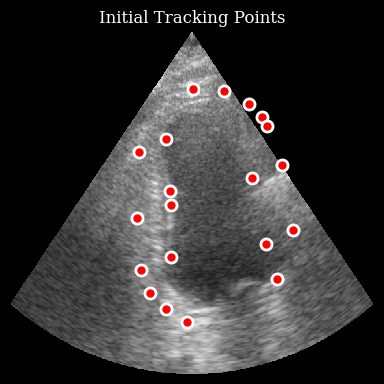

Visualize the initial points

[7]:

fig, ax = plt.subplots(figsize=(4, 4))

ax.imshow(frames[0], cmap="gray", aspect="auto")

ax.plot(

initial_points[:, 1],

initial_points[:, 0],

"ro",

markersize=8,

markeredgecolor="white",

markeredgewidth=2,

)

ax.set_title("Initial Tracking Points")

ax.axis("off")

plt.tight_layout()

plt.show()

../../_images/notebooks_models_speckle_tracking_example_12_0.png